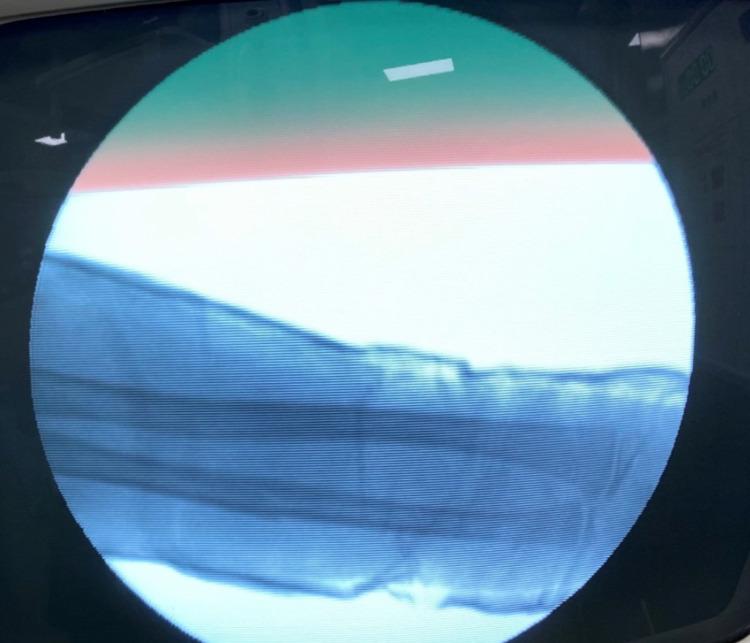

Introduction Fractures in children are extremely common scenarios encountered by orthopedicians. Conservative treatment has been the most preferred choice for the management of diaphyseal forearm fractures. Traditionally, pediatric forearm fractures are treated by above elbow plaster cast with the elbow flexed to 90 degrees. The purpose of this study was to evaluate the functional and radiological outcomes of children treated with closed reduction and extension casting for forearm fractures. Patient and methods This is a prospective study evaluating the functional and radiological outcomes of 30 children of less than the age of 14 years and without pathological fractures, treated with closed reduction and extension casting for forearm fractures, either both radius and ulna or radius or ulna at middle third level, who reported to the Department of Orthopedics, Dr. D.Y. Patil Medical College, Hospital, and Research Center, Pune, India, between September 2019 and March 2022. Results The mean pre-operative angulation in radius (antero-posterior {AP}) was 22.7, radius (lateral {LAT}) was 24.2, ulna (AP) was 31.2, and ulna (LAT) was 29.2. The immediate post-operative angulation of radius (AP) was 0.7, radius (LAT) was 3.2, ulna (AP) was 0.6, and ulna (LAT) was 4.9. Cast status at two weeks, 83.3% had intact cast and 16.7% had loosened casts. Post removal, most patients had a good rotation of motion (ROM) at three and six weeks. Conclusion Casting with extended elbow is much better as compared to flexion casting in the hands of a trainee doctor. Furthermore, chances of loss of reduction are negligible in extension casting as compared to flexion casting.

引言 儿童骨折是骨科医生经常遇到的极为常见的情况。保守治疗一直是治疗肱骨干骨折的最首选方法。传统上,小儿前臂骨折采用屈肘90度的上臂石膏固定治疗。本研究的目的是评估采用闭合复位和伸直位石膏固定治疗前臂骨折的儿童的功能和影像学结果。

患者与方法 这是一项前瞻性研究,评估了2019年9月至2022年3月期间,在印度浦那D.Y.帕蒂尔医学院、医院和研究中心骨科就诊的30名14岁以下且无病理性骨折的儿童的功能和影像学结果,这些儿童因前臂骨折接受了闭合复位和伸直位石膏固定治疗,骨折部位为桡骨和尺骨或桡骨或尺骨的中三分之一段。

结果 桡骨术前平均成角(前后位{AP})为22.7,桡骨(侧位{LAT})为24.2,尺骨(AP)为31.2,尺骨(LAT)为29.2。术后即刻桡骨(AP)成角为0.7,桡骨(LAT)为3.2,尺骨(AP)为0.6,尺骨(LAT)为4.9。两周时石膏情况,83.3%的石膏完整,16.7%的石膏松动。拆除石膏后,大多数患者在三周和六周时运动范围(ROM)良好。

结论 对于实习医生来说,伸直位石膏固定比屈曲位石膏固定要好得多。此外,与屈曲位石膏固定相比,伸直位石膏固定复位丢失的几率可以忽略不计。